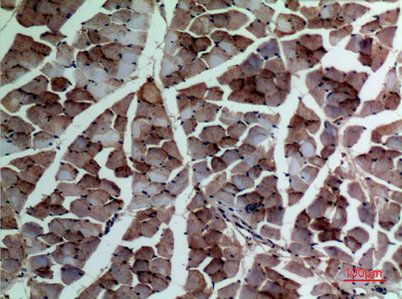

Product name: α-SMA rabbit pAb

Alternative Names: ACTA1; ACTA; Actin, alpha skeletal muscle; Alpha-actin-1; ACTA2; ACTSA; ACTVS; GIG46; Actin, aortic smooth muscle; Alpha-actin-2; Cell growth-inhibiting gene 46 protein; ACTC1; ACTC; Actin, alpha cardiac muscle 1; Alpha-cardiac actinACTA1; ACTA; Actin, alpha skeletal muscle; Alpha-actin-1; ACTA2; ACTSA; ACTVS; GIG46; Actin, aortic smooth muscle; Alpha-actin-2; Cell growth-inhibiting gene 46 protein; ACTC1; ACTC; Actin, alpha cardiac muscle 1; Alpha-cardiac actin

Dilutions: Western Blot: 1/500 - 1/2000. IHC-p: 1:100-300 ELISA: 1/20000. Not yet tested in other applications.

Immunogen: Synthesized peptide derived from the C-terminal region of human α-SMA.